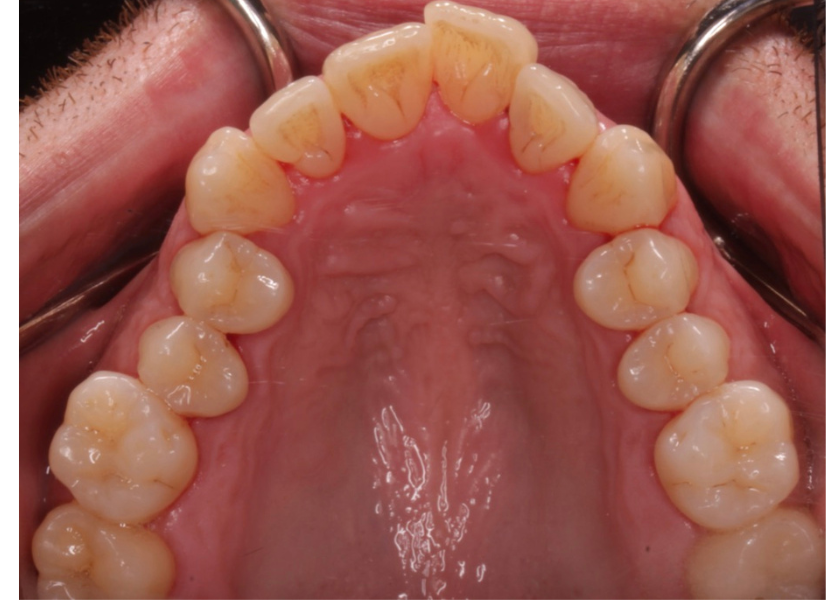

Este paciente acudió a Clínica Dental Urumea para mejorar la estética de su sonrisa. Primero se realizó un tratamiento de ortodoncia con alineadores transparentes Invisalign, para alinear y corregir la mordida cruzada.